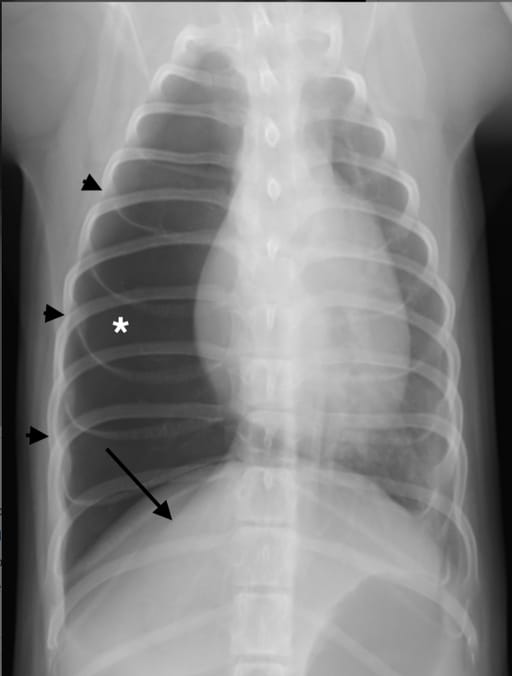

Dorsoventral radiograph of the thorax of a dog with congenital lobar emphysema (CLE) of the right middle lung lobe. Note the enlarged and hyperlucent lung lobe (*), expanded right side of the rib cage (black arrowheads) and compressed right diaphragmatic crus (black arrow). It was not possible to determine which lobe was emphysematous based on the radiographs alone